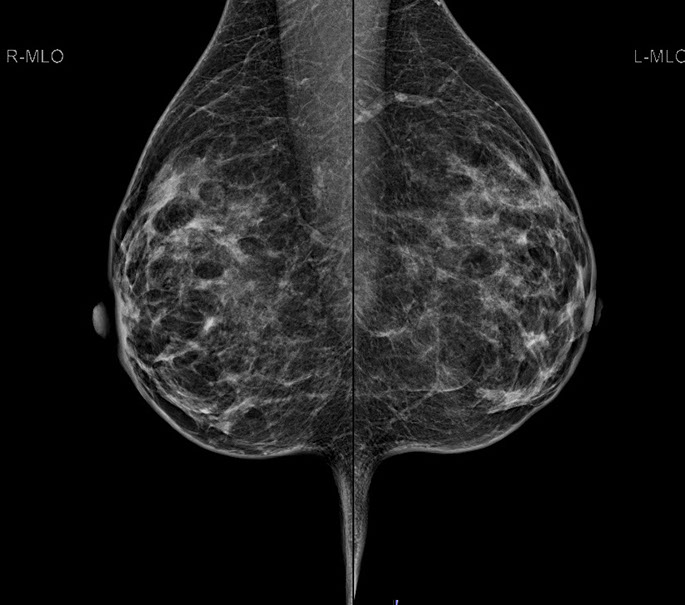

Bei der Mammographie handelt es sich um ein Röntgenverfahren, welches auf einem einfachen Prinzip beruht: Unterschiedliche Gewebestrukturen (Fettgewebe, Bindegewebe, Brustdrüsengewebe) haben eine unterschiedliche Dichte. Die bei der Mammographie verwendete weiche Strahlung wird von einzelnen Gewebekomponenten unterschiedlich absorbiert, woraus unterschiedliche Kontraste im Mammographiebild resultieren.

Mit dieser digitalen Vollfeld-Mammographie – wie sie in der Radiologie Graz St. Peter für Ihre Brustuntersuchung eingesetzt wird – ist ein entscheidender Fortschritt in der Mammographiepraxis gelungen. Die neuen Flat-Panel-Röntgendetektoren bieten eine extrem hohe Quantenausnutzung und ein hohes Auflösungsvermögen.

2.  Bessere Aussagekraft bei dichtem Brustdrüsengewebe

Vor allem junge Frauen bzw. Frauen vor der Menopause haben ein dichtes Brustdrüsengewebe. In der konventionellen Mammographie ließ sich dieses dichte Gewebe oft schlecht darstellen. Aufgrund von Fehlbelichtungen waren Wiederholungsaufnahmen notwendig, die eine zusätzliche Strahlenbelastung mit sich brachten. Die digitale Mammographie kann hingegen auch geringere Kontraste in sehr dichtem Brustdrüsengewebe deutlicher hervorheben und so eine zuverlässigere Diagnostik ermöglichen. Fehlbelichtungen wie bei der alten konventionellen Mammographie werden praktisch ausgeschlossen.

Die Diagnosesicherheit und Möglichkeit einer Brustkrebsfrüherkennung durch die Mammographie, hängt von der Dichte des Brustdrüsengewebes ab. Einteilung der Dichtegrade wurde vom American College of Radiology (ACR) übernommen.

Bei einem Dichtegrad 3 sinkt die Sensivität der Mammographie deutlich, bei Dichtegrad 4 liegt sie unter 50 %. Durch gleichzeitigen Einsatz der Ultraschalluntersuchung wird die Sicherheit in der Diagnoseerstellung jedoch wieder auf

ca. 90 % angehoben.